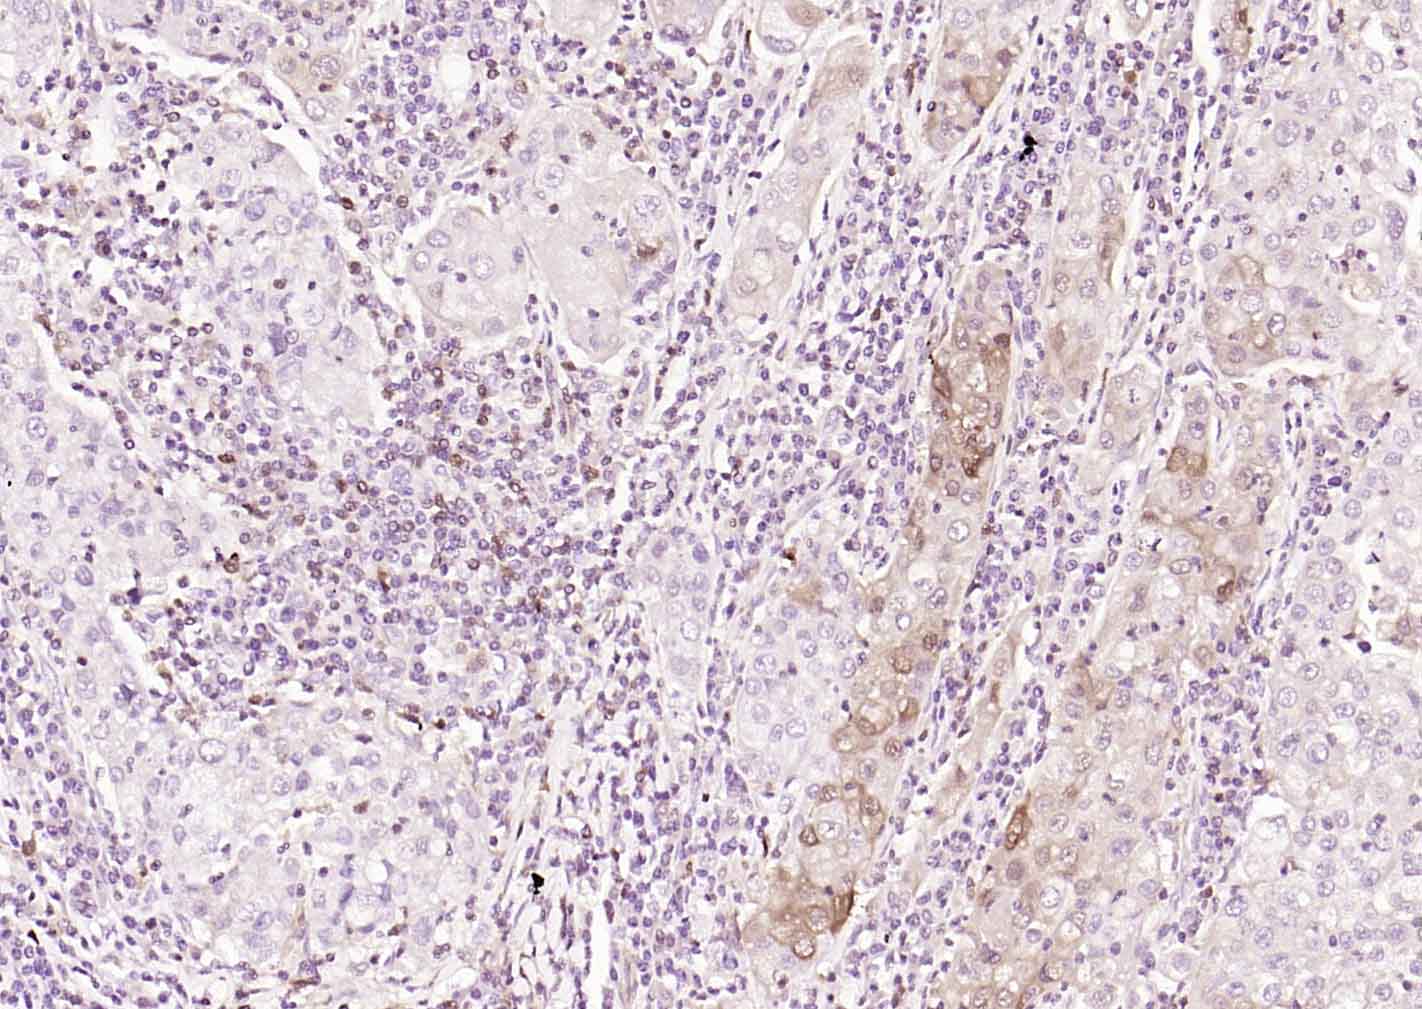

Paraformaldehyde-fixed, paraffin embedded (human gastric carcinoma); Antigen retrieval by boiling in sodium citrate buffer (pH6.0) for 15min; Block endogenous peroxidase by 3% hydrogen peroxide for 20 minutes; Blocking buffer (normal goat serum) at 37°C for 30min; Incubation with (S100A4) Monoclonal Antibody, Unconjugated (bsm-60916M) at 1:100 overnight at 4°C, followed by operating according to SP Kit(Mouse)(sp-0024)instructionsand DAB staining.